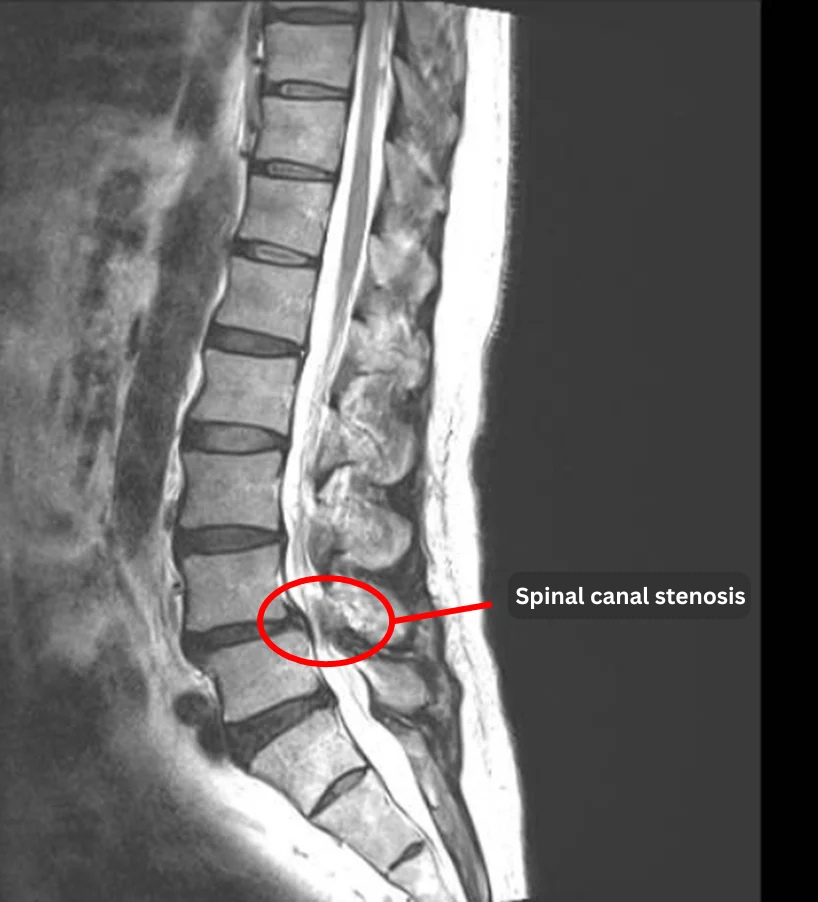

- L1/2, L3/4, L4/5, L5/S1: Disc degeneration

- L4/5: Lumbar spinal canal stenosis

- L4: Anterolisthesis

The above findings were also observed on the imaging.

・These findings indicate that lumbar spinal stenosis at L4/5 is a likely cause of the patient’s primary symptoms.